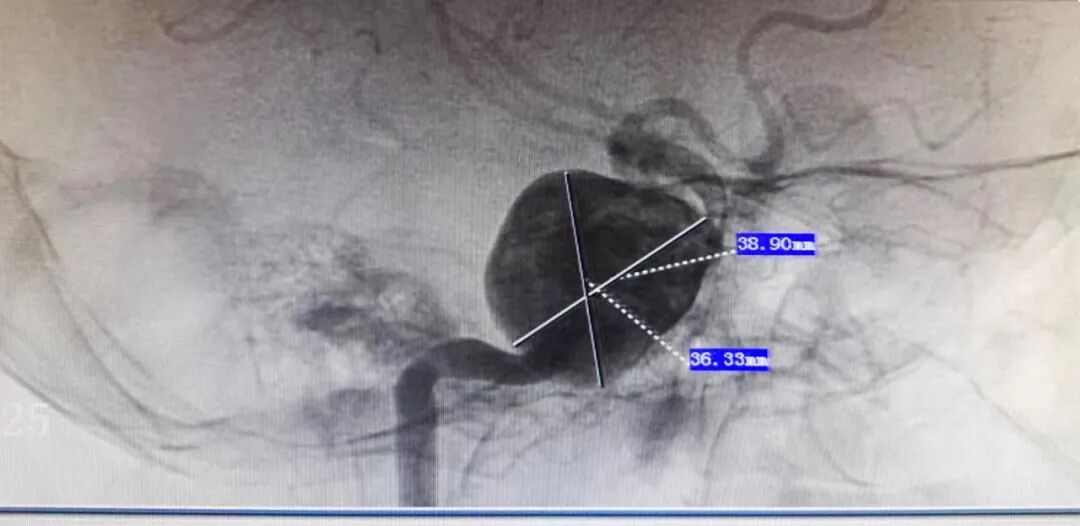

近日,廉江市人民医院神经外科团队在上级专家技术支持下,成功开展了一例高难度右侧颈内动脉海绵窦段巨大动脉瘤血流导向装置密网支架置入手术,术程顺利,患者术后恢复良好,已经顺利出院。患者动脉瘤达(38.9mm×36.33mm),较为罕见,该手术也是廉江市人民医院首例。

入院后,医生发现患者头晕头痛症状明显,右眼裂变小,双侧瞳孔大小不等,影像学明确诊断为:右侧颈内动脉海绵窦段巨大动脉瘤,大小约38.9mm×36.33mm,囊状、宽颈,载瘤动脉扩张为动脉瘤一部分,瘤内血栓形成,瘤颈紧邻眼动脉,载瘤动脉迂曲等,复杂,处理困难。